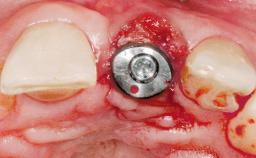

A 33-year-old female patient presented with an upper left central incisor that required extraction after a failed endodontic therapy. The tooth had been traumatized when the patient was a teenager and had undergone several endodontic treatments, including two apicectomy procedures. The patient was in good health and did not smoke. Clinical examination showed that the patient had a high lip line. In full smile, the gingival margins of the upper teeth were visible to the first molars. The gingival margins of central incisors 11 and 21 were only just showing. Examination of tooth 21 confirmed that the tooth was mobile and had hypererupted by 1 mm.

Placement Protocol Immediate implant placement

Socket Morphology Single-root socket

Socket Integrity Damage to one or more bone walls

Bone Volume Damage to one or more socket walls

Bone Augmentation Horizontal|Simultaneous

Augmentation Materials Xenogenous|Membrane